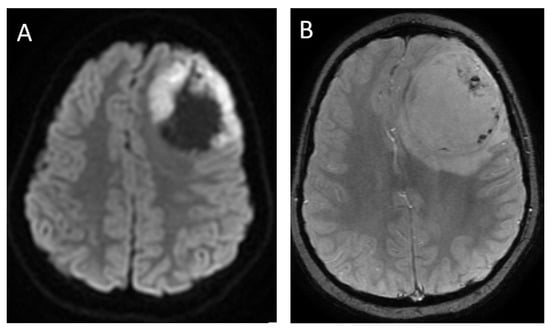

Figure 7.

A 14-year-old male with H3 G34R mutant high-grade glioma. Axial DWI (A), axial SWI (B), axial T2 (C) and coronal post-contrast T1-weighted (D) images demonstrate a large mass in the right parieto-temporal lobes, with diffusion restriction of the solid portions, central areas of blood products and/or mineralization (arrow), isointense T2 signal with central necrosis (curved arrow), and heterogenous post-contrast enhancement.